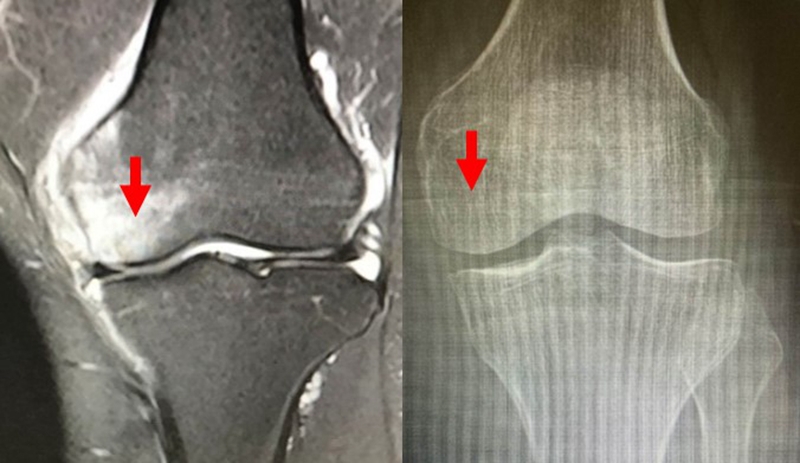

病例2:女,69岁,主诉左膝关节内侧疼痛1月余。2017年11月X光见右膝股骨髁负重区的软骨下区域出现了椭圆形透亮影,MR检查见股骨内侧髁骨坏死,合并内侧半月板外突和后角层裂,半月板相对突出百分比(RPE)25.32%,矢状位病变区域前后径为23.96mm,关节线会聚角6°。

予克氏针钻减压,消炎止痛药物口服、静滴唑来膦酸钠注射液,避免负重6周,后改部分负重至3个月,患者依从性差。2018年1月复查MR见骨髓水肿少许吸收,坏死区扩大,半月板相对突出百分比(RPE)33.53%,矢状位病变区域前后径为26.89mm,患者仍有膝关节疼痛症状,建议行手术治疗,患者拒绝手术后失访。